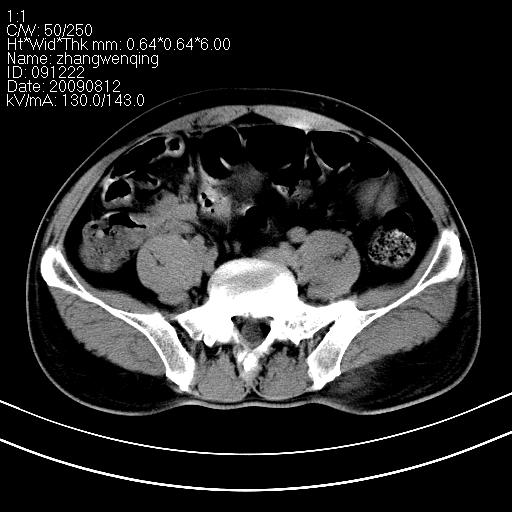

标题: CT21569:M,54Y,右侧中腹部疼痛,IVP示右侧输尿管中下段充盈缺 [打印本页]

标题: CT21569:M,54Y,右侧中腹部疼痛,IVP示右侧输尿管中下段充盈缺

右输尿管下段扩张积水。左下腹部肠管间质瘤不除外。

看不清,应打个增强,右侧输尿管扩张,右侧肠系膜上好像占位。

右侧输尿管扩张积水,考虑结石,最好做个增强除外输尿管占位性病变

右输尿管下段扩张积水,壁增厚、边缘不光整,考虑炎性改变

ct21569和ct21569b(增强)结果:阑尾腺癌,侵犯回盲部及输尿管中段。手术切除部分升结肠、回肠及受侵4cm之输尿管,做回-横结吻合,输尿管支架置放术并吻合,术后病理腺癌,阑尾来源可能性大。

右侧输尿管扩张似见软组织密度影,输尿管占位不能排除。